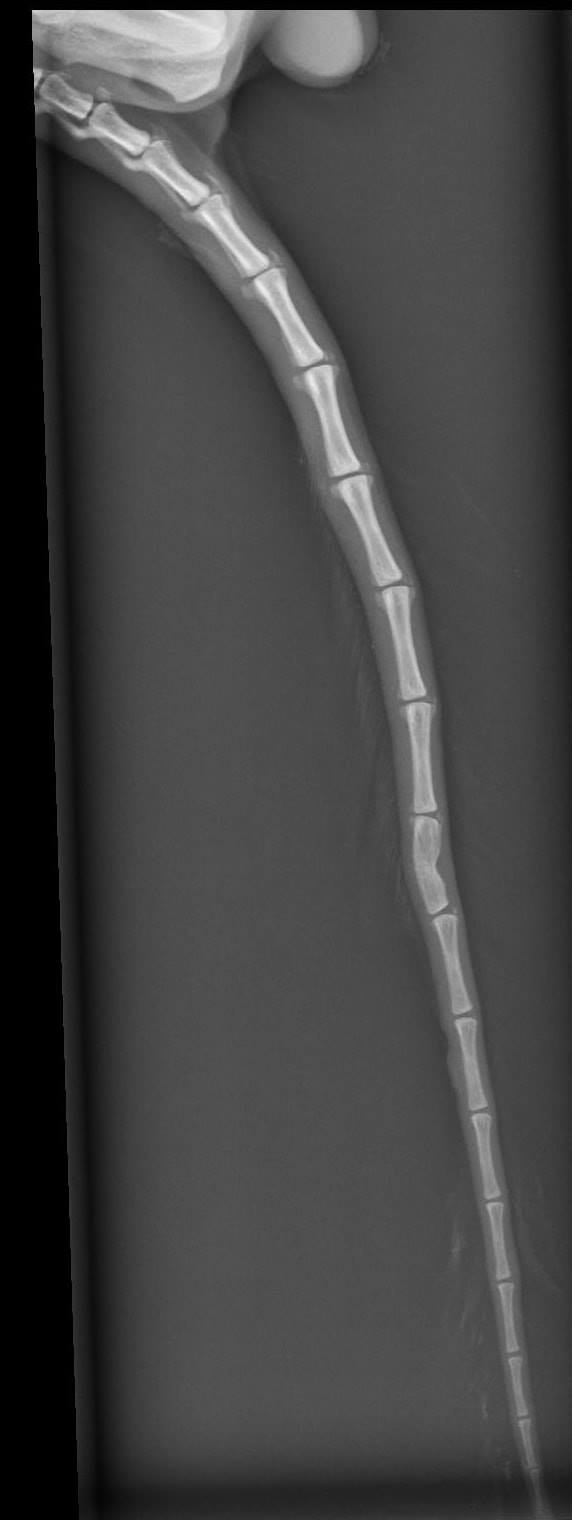

🔸Ocásek je naštěstí vážně zlomený jen 1x. To ostatní jsou jen "šrámy a prkotiny". Zvládli jsme i SONO a RTG.